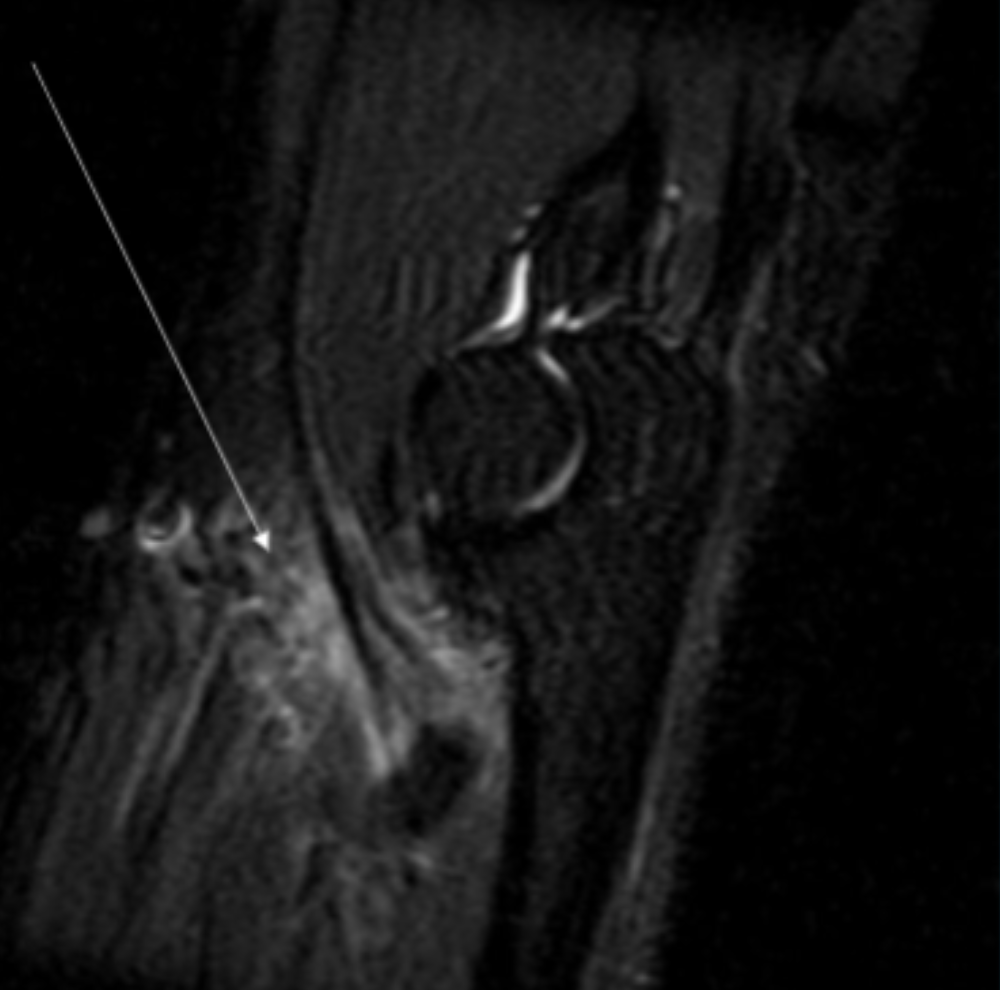

Describe the pathology indicated by the arrow (Cor T1 FS +C).

Osteosarcoma